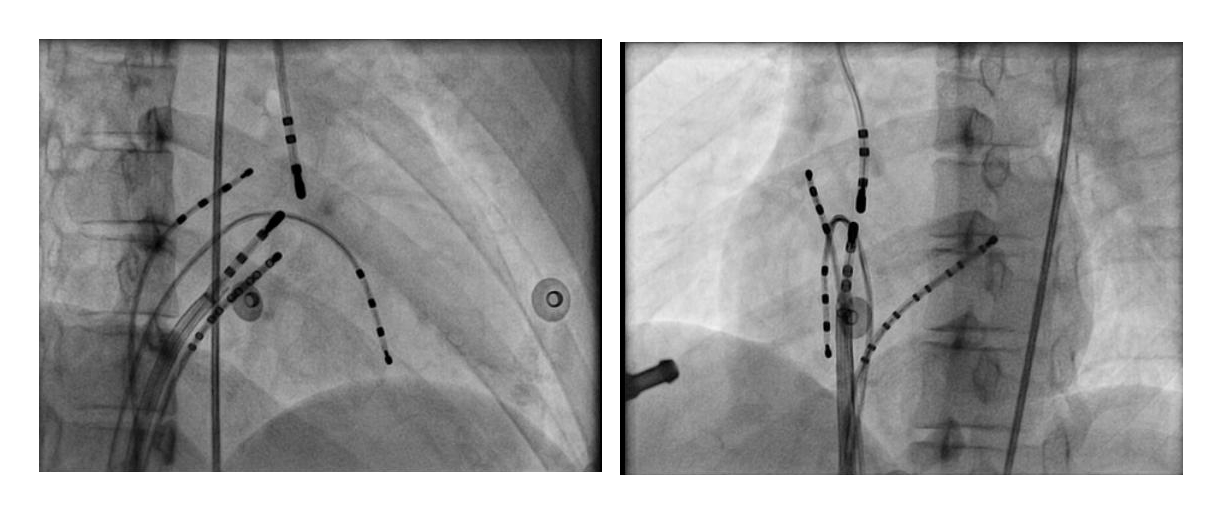

Mapping in diverticulum

diverticulum.jpg

med_lat_div.jpg

signals.jpg